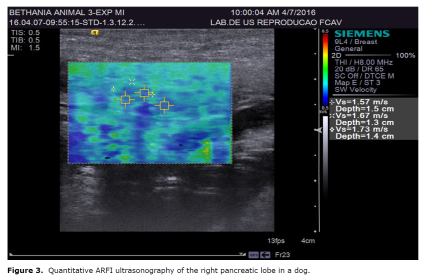

ARFI elastography provides quantitative and qualitative measurements of tissue stiffness with low interobserver variability (22). Quantitative ARFI employs a primary acoustic pulse towards the region of interest, promoting the formation of propagating pressure waves capable of deforming tissues, and the speed of propagation of these pressure waves (shear) is then measured. The propagation velocity and attenuation of waves are related to the stiffness and viscoelasticity of the tissue, with greater speed being observed in harder tissues (23)(Figure 3).

A study using 52 healthy human patients and 46 with chronic pancreatitis evaluated by ARFI elastography reported that the pancreas of patients with chronic disease showed higher elasticity than those of healthy patients. Quantitative values obtained from these patients were 0.78 to 1.40 m/s. The positive, negative, sensitivity, and specificity predictive values obtained were 69, 78, 75, and 72%; respectively (30). In another study, the quantitative mean values reported were 1.28 m/s in normal pancreas, 1.25 m/s in chronic inflammatory disease, and 3.28 m/s in acute inflammatory disease (31).